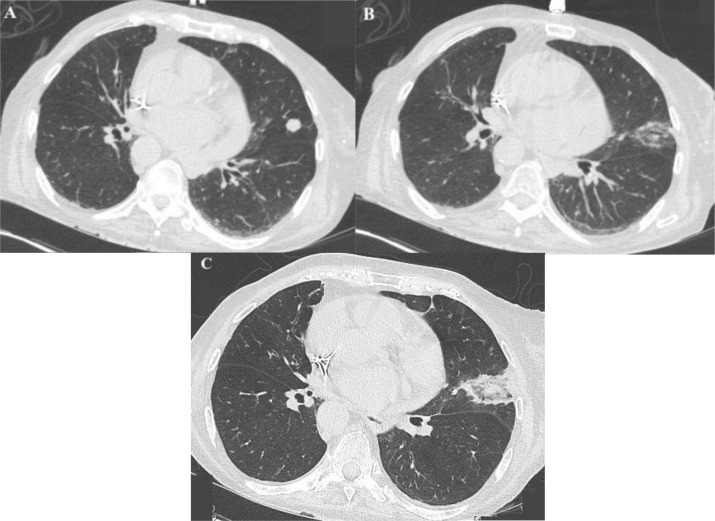

肺类癌是罕见的,可导致严重的副肿瘤综合征。本文报道一例78岁的ACTH依赖性库欣综合征患者不能手术,经微波消融术成功治疗。该手术导致临床迅速改善,无并发症和放射学稳定性。教学要点:微波消融术作为一种微创治疗选择,为不能手术的患者提供了一种有效的肿瘤控制策略。

Pulmonary carcinoid tumors are rare and may lead to severe paraneoplastic syndromes. A case is reported of an inoperable 78‑year‑old patient with ACTH‑dependent Cushing's syndrome successfully treated with microwave ablation. The procedure resulted in rapid clinical improvement without complications and radiological stability. Teaching point: The role of microwave ablation as a minimally invasive alternative for selected inoperable patients, offering an effective tumor control strategy with minimal morbidity.